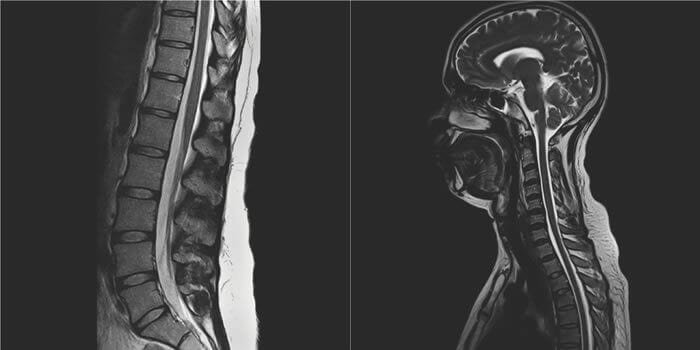

Ressonância magnética da coluna

A ressonância magnética da coluna é um exame de imagem muito sofisticado que pode mostrar detalhes anatômicos da medula espinhal, das raízes nervosas, discos, ligamentos, tecidos adjacentes e espaços.

Os exames podem ser ajustados para mostrar diferentes tecidos, inclusive seu conteúdo líquido, o que é importante para determinar degenerações discais, infecções e tumores. O objetivo de todos os estudos diagnósticos é descobrir padrões ou confirmações entre os vários exames que apontem para um diagnóstico claro.